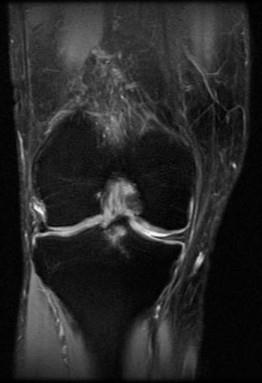

问题 男,50岁,膝关节侧方疼痛,请结合影像图像,选择最可能的诊断 ( )

选项 A、前十字韧带囊肿 B、膝关节腔积液 C、滑膜型关节结核 D、前十字韧带黏液样变性 E、化脓性关节炎

答案 D